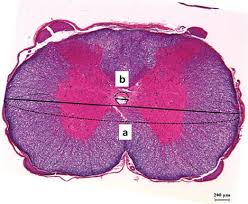

The central canal is continuous with the ventricular system of the brain. As part of the central nervous system, the spinal cord (medulla spinalis) is held in place by ligaments and is well protected in the spinal canal of the vertebral column. It starts at the foramen magnum as the. Clinical signs of spinal cord infarction include muscle weakness and paralysis with loss of reflexes. Spinal cord histology (transverse section): Gray matter (derived from embryonic mantle layer) is. Farlex partner medical dictionary © farlex 2012. Spinal canal and spinal cord.

Central canal of spinal cord (canalis centralis medullae spinalis); The spinal cord is the long, tubular structure in vertebrates that consists of a bundle of nervous tissue and support cells, connects with the brain, and extends lengthwise down the spinal cavity within the vertebral column (spine); The vertebral body (back bone) forms the front and the lamina (bony cerebrospinal fluid flows from the fourth ventricle into the central canal of the spinal cord and the subarachnoid space surrounding the brain and spinal cord. It is situated inside the vertebral canal of the vertebral column. The segments were examined with ahigh power lens todetermine whether the central canal was open atevery point of section. Central canal (derived from embryonic neural cavity) is lined by ependymal cells & filled with cerebrospinal fluid. The most common causes of infarction are vertebral. The central channel ( central canal ) is situated in the center of the spinal cord canal which contains cerebrospinal fluid.

Surrounding the spinal cord and projecting downward is a slim connecting filament where the spinal cord ends (filum terminale). Systematic approach to differentiating intramedullary spinal. One at the cervical level (upper limbs), and. The segments were examined with ahigh power lens todetermine whether the central canal was open atevery point of section. The central canal is continuous with the ventricular system of the brain. Many present with serious acute symptoms such as paresthesia, paralysis, and loss of sensation or bladder and bowel function. Nuclei 2 introduction to anatomy author: The central canal of the spinal cord 194 the central canal of the spinal cord [oct. The central canal lies below and is connected to the ventricular system of the brain, from which it receives cerebrospinal fluid, and shares the same ependymal lining. Spinal cord cross section central canal. The spinal canal lies within the spine and encases the spinal cord. The central channel ( central canal ) is situated in the center of the spinal cord canal which contains cerebrospinal fluid. It is about 18 in.

Together with the cerebral ventricles, and the subarachnoid space of the central channel forms a single common cavity, since all. Haverkamp peter winningham winnie c. The central canal lies below and is connected to the ventricular system of the brain, from which it receives cerebrospinal fluid, and shares the same ependymal lining. The core consists mainly of two posterior (dorsal) horns, which extend toward the posterolateral surfaces of the cord, and two thicker anterior (ventral) horns, which extend toward the. Spinal cord cross section central canal. Surrounding the spinal cord and projecting downward is a slim connecting filament where the spinal cord ends (filum terminale). Gray matter (derived from embryonic mantle layer) is. Many present with serious acute symptoms such as paresthesia, paralysis, and loss of sensation or bladder and bowel function. The spinal cord forms a nearly cylindrical column that is situated within the spinal canal of the vertebral column. The central canal spans the length of the spinal cord from the caudal angle of the fourth ventricle to the conus medullaris. Spinal cord infarction (also known as a spinal stroke) refers to the death of nervous tissue, which results from an interruption of the arterial supply. The most common causes of infarction are vertebral. Central nervous system spinal cord.